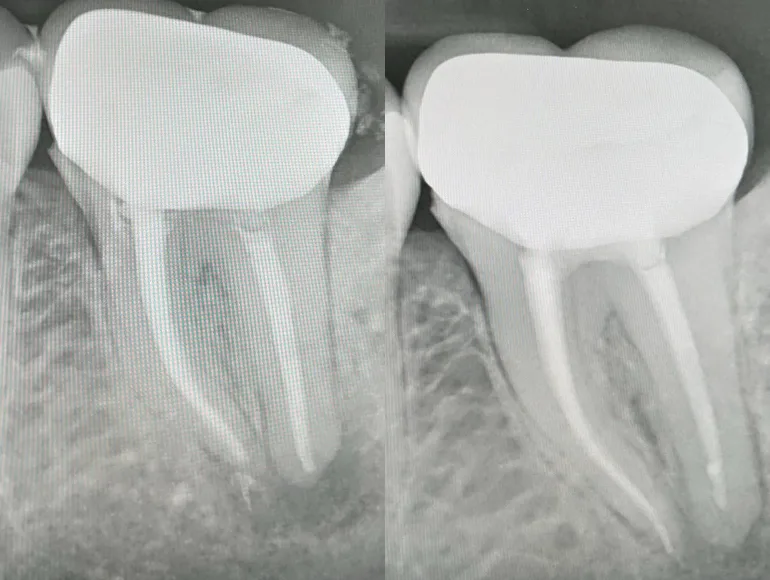

Extreme Curved Roots

Case by Dr. Taha Azimaie: Rootcanal treatment in extreme curved roots is technique sensitive procedure and require skills and right equipments.